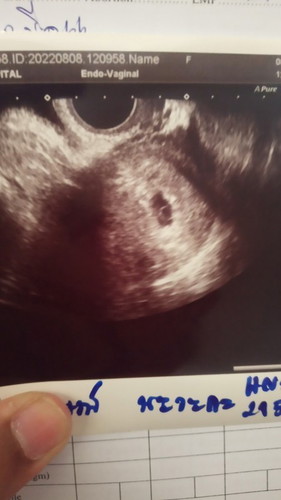

ซาวผ่านช่องคลอด

6วีค3วัน แม่บ้านไหนเจอน้องแล้วหรือยังคะ บ้านนี้หมอบ้านเจอไข่ รอนัดอีก2อาทิต